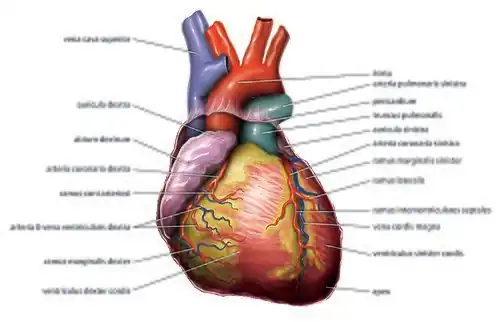

Rechte und linke Herzhälfte bestehen jeweils aus einer Kammer (lat. Ventriculus cordis, (Herz-)Ventrikel, kurz RV und LV) und einem Vorhof (Atrium, RA und LA). Getrennt werden die Räume der Herzhälften vertikal durch die Herzscheidewand (Septum). Diese wird in die Vorhofscheidewand (Septum interatriale, Vorhofseptum) und die Kammerscheidewand (Septum interventriculare, Ventrikelseptum) unterteilt. Außen ist die Grenze zwischen Herzkammern und Vorhöfen durch die Herzkranzfurche (Sulcus coronarius) ersichtlich, in welcher die Herzkranzgefäße verlaufen. Die Grenze zwischen beiden Herzkammern ist von außen durch zwei Furchen – Sulcus interventricularis subsinuosus und Sulcus interventricularis paracoronalis sichtbar. In den Herzkammern bildet die Herzmuskulatur netzartige kleine, in das Innere hineinragende Bälkchen, die als Fleischbalken (Trabeculae carneae, Singular Trabecula carnea) bezeichnet werden.

Das Blut kann zwischen den Herzräumen nur in eine Richtung fließen, da sich zwischen den Vorhöfen und den Kammern sowie zwischen den Kammern und den sich anschließenden Gefäßen Herzklappen befinden, die wie Rückschlagventile arbeiten. Alle vier Klappen des Herzens befinden sich ungefähr in einer Ebene, der Ventilebene, und sind gemeinsam an einer Bindegewebsplatte, dem Herzskelett, aufgehängt. Innerhalb der Kammern und Vorhöfe finden sich Muskelzüge, die in die Hohlräume hervorragen – die Papillarmuskeln und die Musculi pectinati.

In den rechten Vorhof münden die obere und untere Hohlvene (Vena cava superior und inferior). Sie führen das sauerstoffarme Blut aus dem großen Kreislauf (Körperkreislauf) dem Herzen zu. Zwischen rechtem Vorhof und rechter Kammer befindet sich die Trikuspidalklappe, die bei der Kammerkontraktion einen Rückstrom des Blutes in den Vorhof verhindert. Von der rechten Herzkammer aus fließt das Blut über einen gemeinsamen Stamm (Truncus pulmonalis) in die beiden Lungenarterien. Der Rückfluss in die rechte Kammer wird durch die taschenförmige Pulmonalklappe verhindert. Die Lungenarterien führen das sauerstoffarme Blut dem Lungenkreislauf (kleiner Kreislauf) zu.

Durch meist vier Lungenvenen fließt das in der Lunge mit Sauerstoff angereicherte Blut in den linken Vorhof. Von hier aus gelangt es über eine weitere Segelklappe, die Mitralklappe, zur linken Kammer. Der Ausstrom erfolgt durch den sogenannten linksventrikulären Ausflusstrakt (LVOT) über eine weitere Taschenklappe (Aortenklappe) und die Hauptschlagader (Aorta) in den Körperkreislauf.

Herzkranzgefäße

Aus dem Anfangsteil der Aorta entspringen die rechte und linke Herzkranzarterie (Koronararterien). Sie versorgen den Herzmuskel selbst mit Blut. Die Herzkranzarterien sind so genannte „funktionelle Endarterien“. Dies bedeutet, dass eine einzelne Arterie zwar mit anderen Arterien verbunden ist (Anastomosen), dass diese Verbindungen jedoch zu schwach sind, um bei Mangelversorgung eine Durchblutung des Gewebes auf einem anderen Weg zu gewährleisten. Fällt also eine Arterie aufgrund einer Blockade oder einer anderen Störung aus, kommt es in dem von dieser Arterie versorgten Gebiet zu einem Absterben von Gewebe.

Die linke Koronararterie (Arteria coronaria sinistra, left coronary artery, LCA) versorgt die Herzvorderseite. Sie teilt sich in einen Ramus interventricularis anterior (RIVA, left anterior descending, LAD) und einen Ramus circumflexus (RCX).

Die rechte Koronararterie (Arteria coronaria dextra, right coronary artery, RCA) gibt die A. marginalis dextra ab, welche die freie Wand der rechten Herzkammer versorgt. Am „Herzkreuz“ (Crux cordis) teilt sie sich in den Ramus interventricularis posterior und den Ramus posterolateralis dexter. Die rechte Koronararterie versorgt auch einen wichtigen Teil des Erregungssystems (Sinusknoten, Atrioventrikularknoten).

Es gibt drei große Koronarvenen, die in den Sinus coronarius des rechten Vorhofs münden und das sauerstoffarme Blut aus dem Herzmuskel abführen. Die große Herzvene (V. cordis magna) verläuft auf der Vorderseite, die mittlere Herzvene (V. cordis media) auf der Hinterseite und die V. cordis parva am rechten Herzrand. Ein kleiner Teil des sauerstoffarmen Blutes wird über die Thebesius-Venen direkt in die Ventrikel entleert.